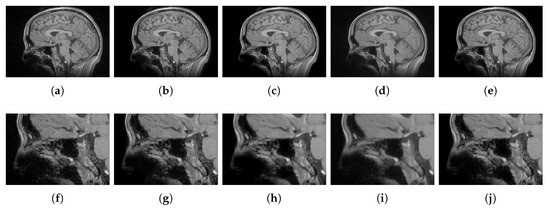

4.2.1. Synthetic Data

4.2.2. Real Data